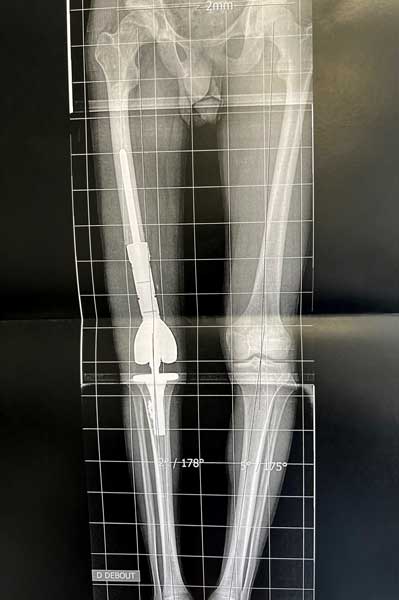

Dès 2006, il a démontré la possibilité de réaliser simultanément deux prothèses de hanche sur le même patient (références 23 à 28), stratégie qui est désormais utilisée par le Docteur Jean-Luc Raynier, et il a mis en évidence les limites des cupules de resurfaçage de hanche (référence 29). Il est également spécialiste de la reconstruction osseuse par Ingénierie tissulaire, sujet de sa thèse de science, objet de nombreuses publications internationales depuis 2005 (références 30 à 36). Enfin, le Professeur Trojani est spécialisé dans les interventions exceptionnelles en chirurgie tumorale, au niveau du genou et du bassin (Figures 3 à 5).

Figure 3 : chirurgie de résection complète du fémur avec mise en place d’une prothèse de fémur total, c’est-à-dire simultanément d’une prothèse de hanche et d’une prothèse de genou, du fait d’une tumeur osseuse atteignant tout le fémur (Sarcome d’Ewing).